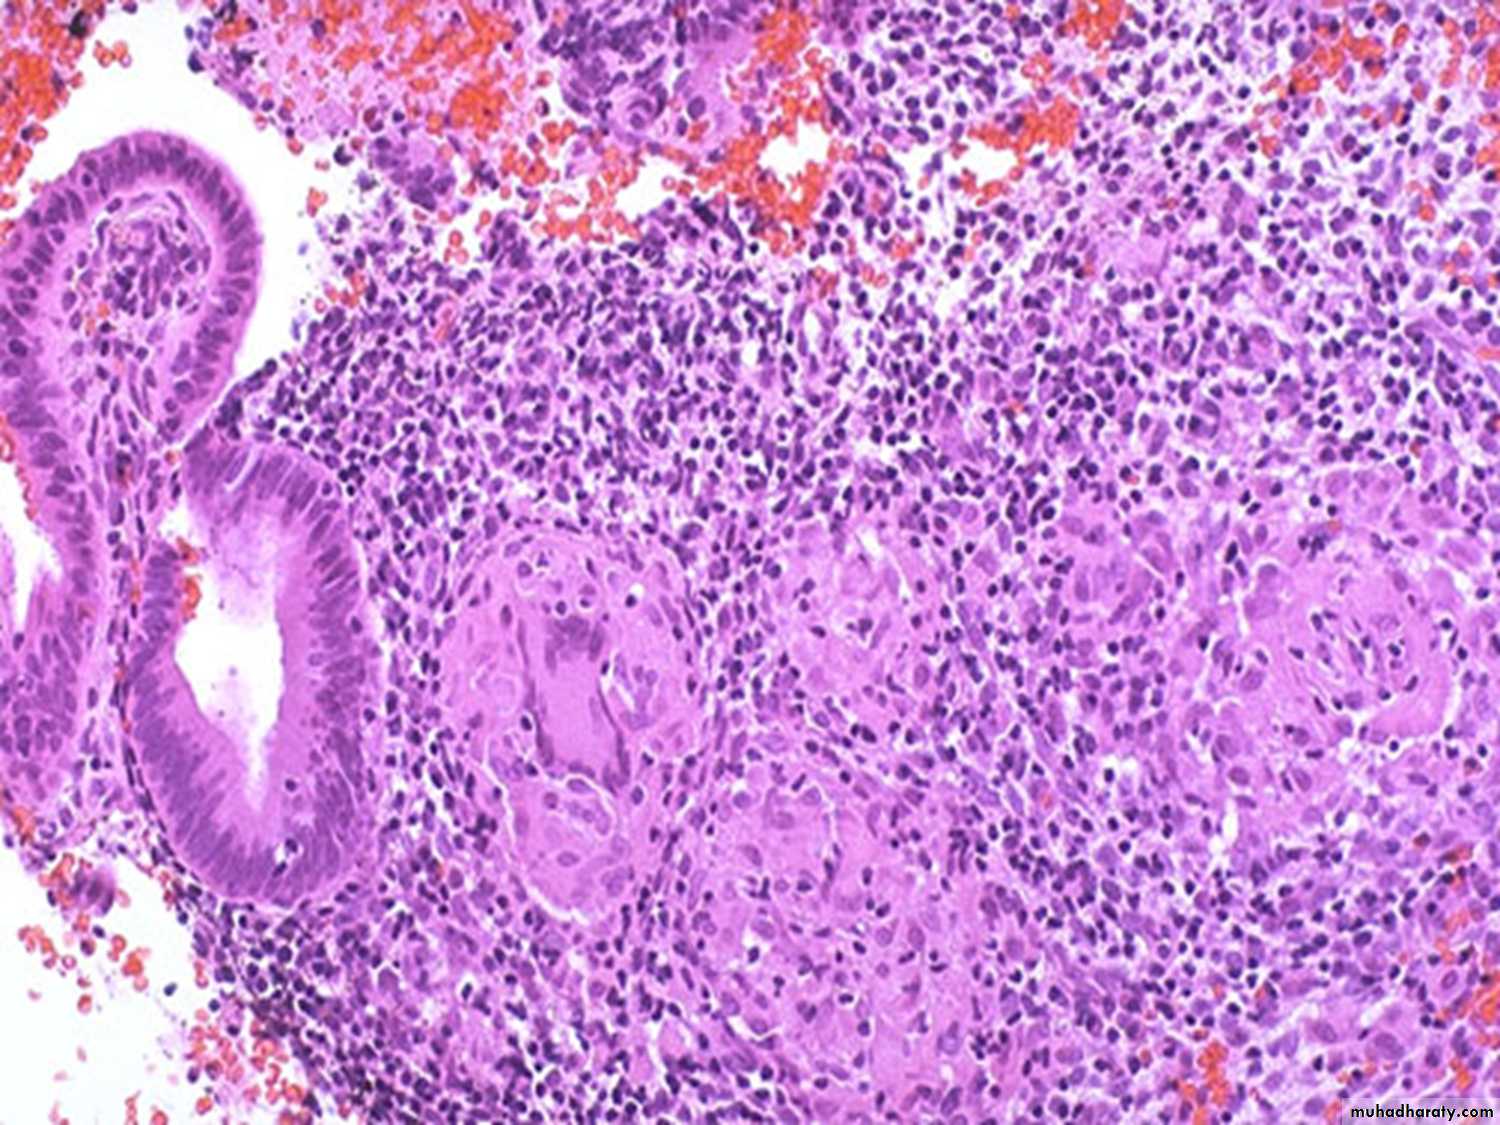

chronic cervicitis:

Small round dark lymphocytes are seen in the submucosa, and there is also hemorrhage.Endocervical polyp composed of a dense fibrous stroma covered with endocervical columnar epithelium.